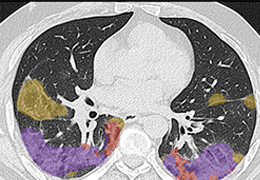

成像智能。

Eclipse 成像智能功能提供强大的处理能力和最佳质量的影像,同时减少质量错误并提高剂量效率。

凭借 AI、专有算法和先进的影像处理能力,提供出色的影像质量和无与伦比的诊断信心。